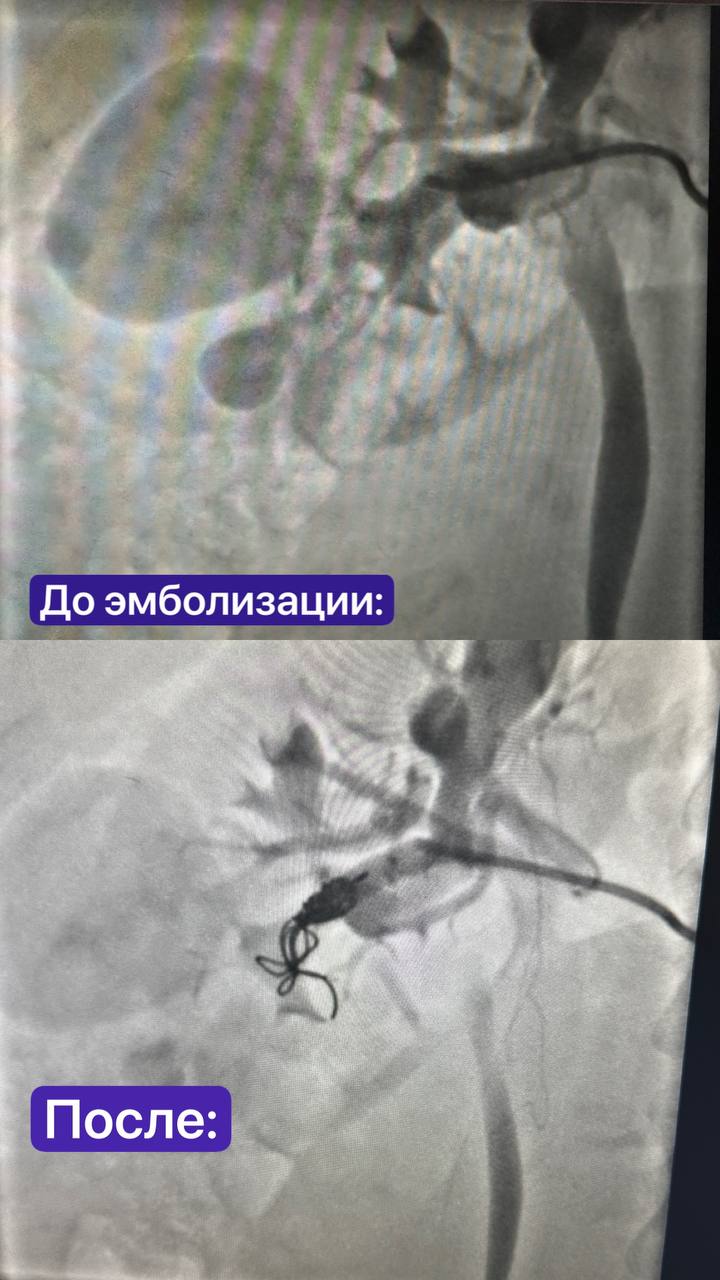

Пришлось направить Алину на КТ – пациентка не сразу согласилась из-за опасений за малыша. Срок был всего 33 недели, но речь шла уже не только о жизни ребёнка, но и о жизни матери. Доктора обнаружили гематому от разорвавшейся аневризмы и еще одну аневризму внутри большой опухоли почки. Это были так называемые истинная и ложная аневризмы.

Истинная, к счастью, не разорвалась. А ложная – сформировалась, как предполагают врачи, в результате повреждения сосуда после травмы Алины. То есть в месте удара сосуд разорвался, случилось кровоизлияние, которое «осумковалось» и сформировалась гематома. В любой момент эта гематома могла разорваться и тогда произошло бы кровоизлияние в брюшную полость.

Несмотря на срок беременности, вес малыша был приличным - кесарево сечение на этом сроке было возможным. Заведующий отделением РХМДЛ №1 Андрей Юрьевич Терегулов эмболизировал артерию, что позволило избежать разрыва второй аневризмы и «обесточить» опухоль, а бескровная методика хирурга-онколога Ивана Борисовича Кутового и уролога Рамиля Шамилевича Гильмутдинова дала возможность удалить образование, сохранив почки.